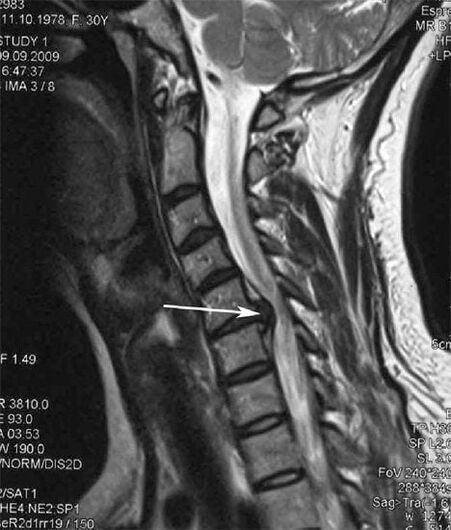

În stadiile inițiale, osteocondroza este detectată prin RMN. Mai târziu, patologia poate fi diagnosticată folosind radiografie. Pe radiografiile coloanei cervicale, devin vizibile o scădere a distanței dintre vertebre, modificări patologice ale articulațiilor fațetelor și osteofitoza.

Mulți oameni se plâng că nu își pot întoarce gâtul din cauza durerii severe care apare după ce ridică brusc ceva greu. Acest fenomen indică formarea unei hernie de disc. Cauza durerii în spate, gât și membru superior este ciupirea uneia dintre rădăcinile nervoase care ies din măduva spinării.